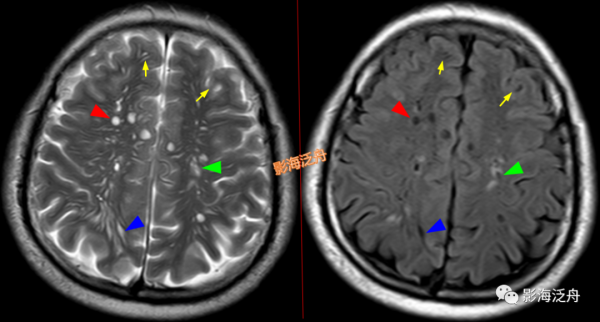

左側基底節區腔梗灶(紅箭頭),儘管後部的那個病灶看起來有點圓,但在Flair序列病灶周圍可以看到非常明顯的高訊號(綠箭),代表區域性膠質增生,證明其為慢性期腔梗灶而非擴大的VR腔隙,其餘病變(黃箭)為對稱性分佈,呈斑點狀或長條狀,Flair序列灶周無高訊號,診斷VR腔隙更為合理。

![]()

在大體標本上對照觀察腔梗灶(紅箭頭)與擴大的VR腔隙(黃箭頭)。